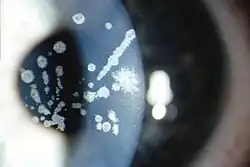

Granular corneal dystrophy type I, Numerous irregular shaped discrete crumb-like corneal opacities

Granular corneal dystrophy type II, Variable sized crumb-like opacities in the corneal stroma that have become fused in areas giving rise to elongated and stellate shapes

Granular corneal dystrophy is diagnosed during an eye examination by an ophthalmologist or optometrist. The lesions consist of central, fine, whitish granular lesions in the cornea. Visual acuity is slightly reduced.